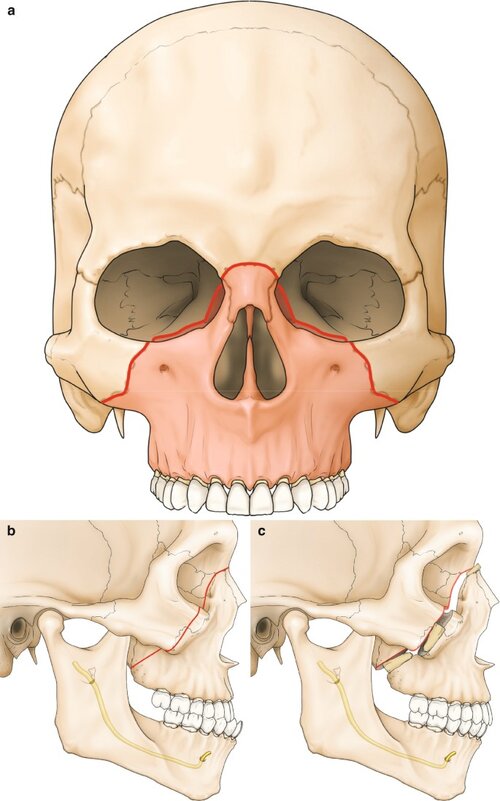

OR, in order to achieve lateral orbital rims that are back-set, do you need [LEFORT 2] as well first ? ik there many types of LEFORT 2 cuts, from giants facial depth thread, he only moves the nasal part anteriorly, [NOT] the medial canthus and the medial/inner section of infraobital a lefort 2 usually does, giant usually advices to get obo+tripod before leforts, bsso etc, correct me if im wrong giant

step 1 : you need to get LeFort 2 modified to be in front of the medial canthus and lacrimal system advancement

OR, in order to achieve lateral orbital rims that are back-set, do you need [LEFORT 2] as well first ? ik there many types of LEFORT 2 cuts, from giants facial depth thread, he only moves the nasal part anteriorly, [NOT] the medial canthus and the medial/inner section of infraobital a lefort 2 usually does, giant usually advices to get obo+tripod before leforts, bsso etc, correct me if im wrong giant

step 1 : you need to get LeFort 2 modified to be in front of the medial canthus and lacrimal system advancement